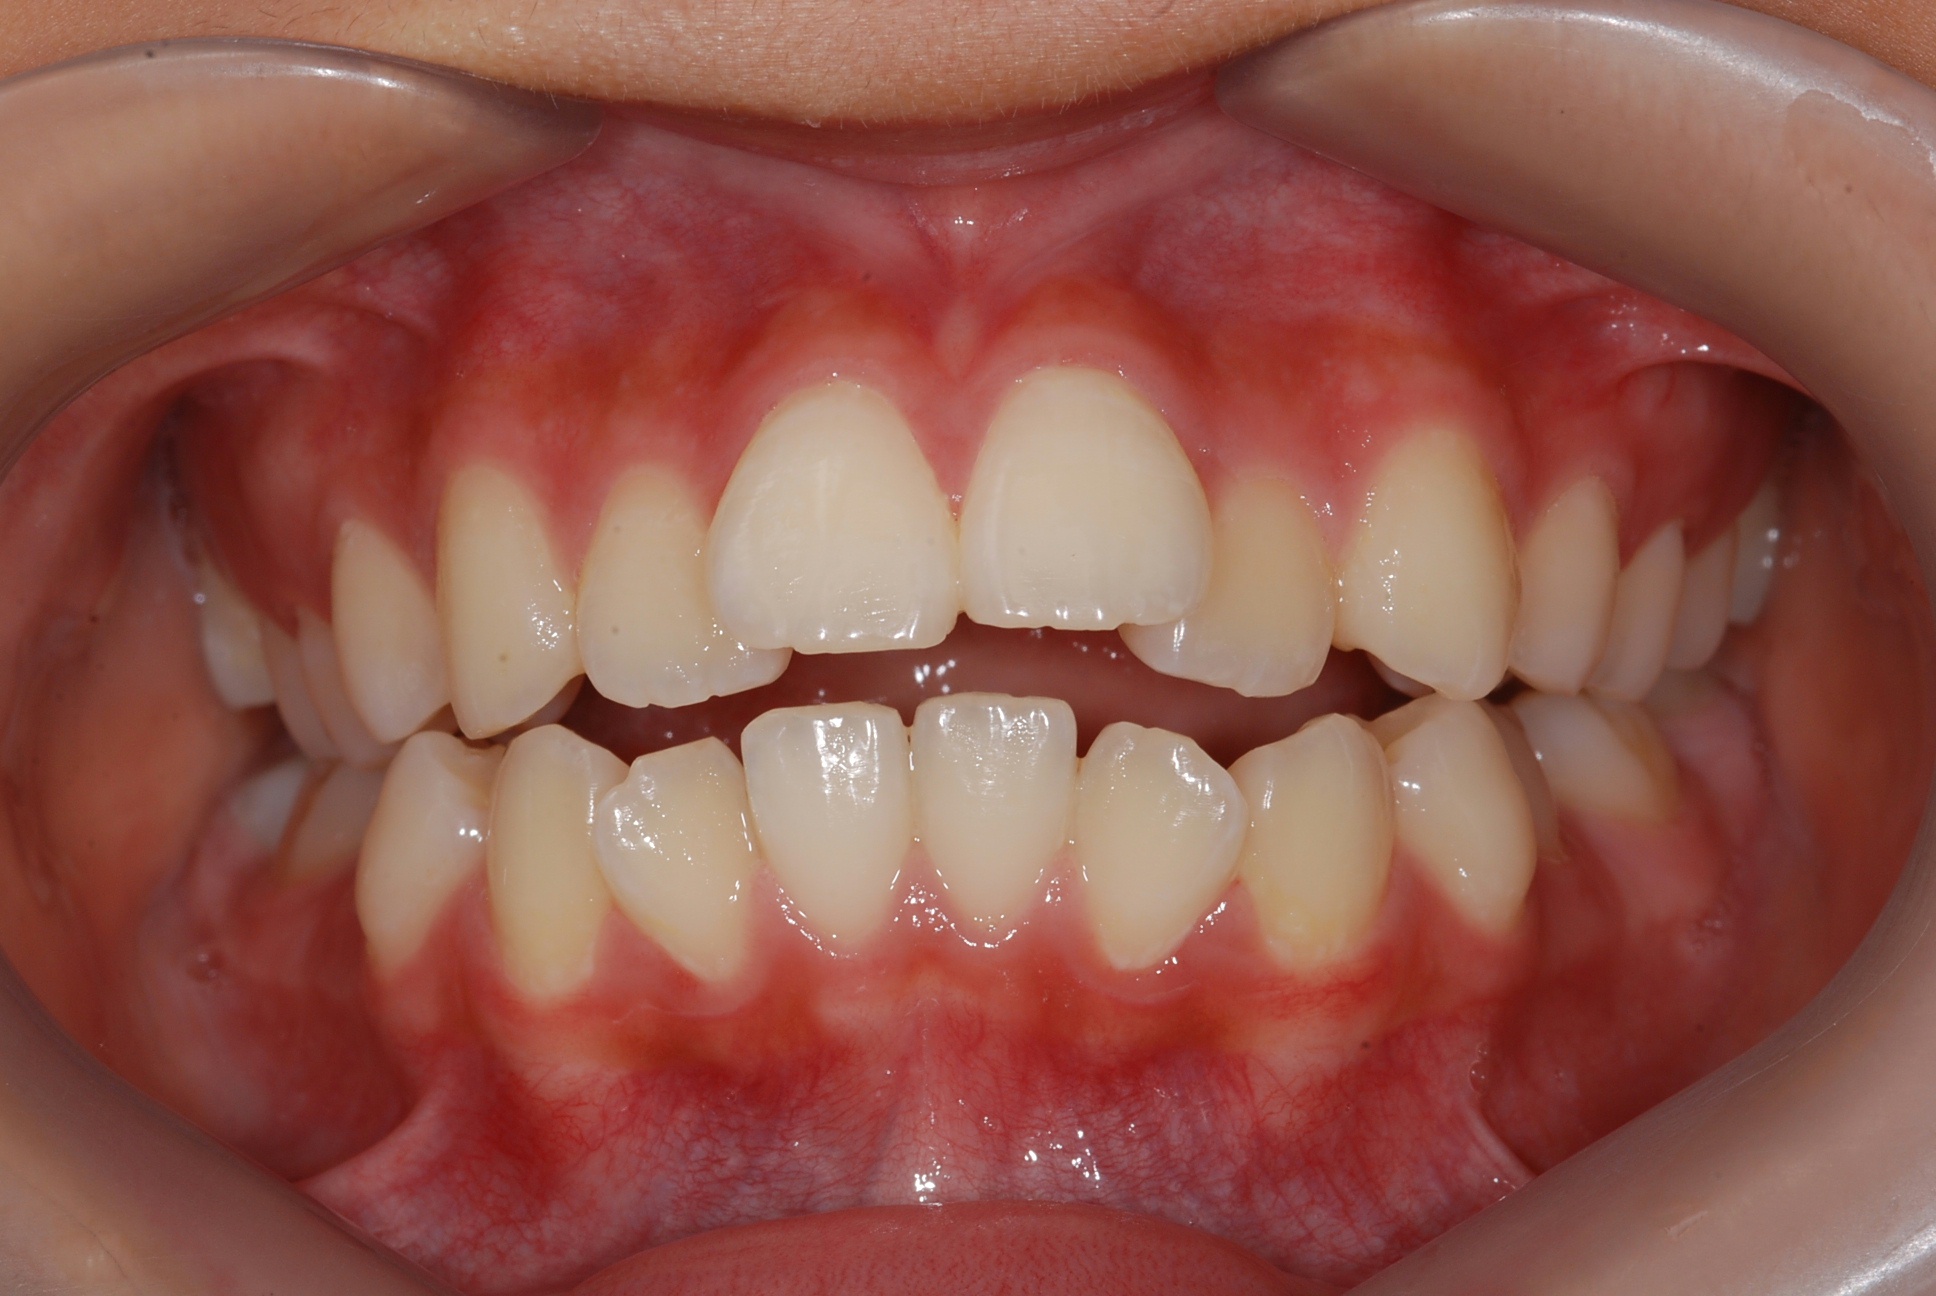

치료 전 사진입니다.